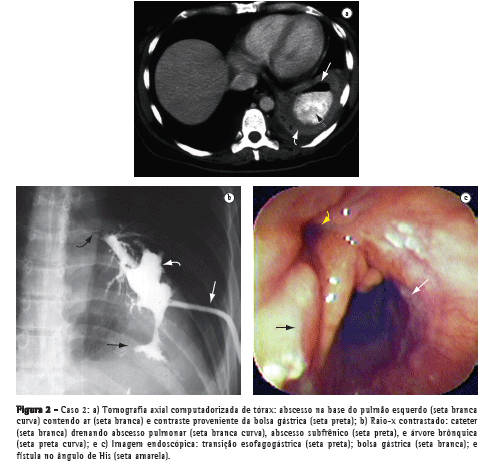

Uma paciente com 44 anos de idade foi submetida à gastroplastia vertical com anel (sleeve gastrectomy) por videolaparoscopia, evoluindo com fístula gástrica e cinco episódios de abscesso subfrênico durante 8 meses. Seu quadro clínico se iniciava com dor no ombro esquerdo e evoluía com febre, tosse, leucocitose, queda do estado geral e perda de peso excessiva. Os dois últimos episódios foram acompanhados de tosse com expectoração purulenta e a tomografia axial computadorizada de tórax diagnosticou abscesso na base pulmonar esquerda (Figura 2a), secundário a abscesso subfrênico a partir do ângulo de His, e estenose gástrica ao nível do anel e da incisura angularis. O abscesso pulmonar proveniente da fístula gastrobrônquica foi drenado através de cateter visualizado em radiografia contrastada (Figura 2b) e a imagem endoscópica mostra o orifício interno da fístula no ângulo de His (Figura 2c).

A paciente recebeu acompanhamento especializado de um pneumologista, um endoscopista e um cirurgião, sendo tratada por meio de antibioticoterapia, fisioterapia respiratória e suporte nutricional por sonda nasoenteral. Além disso, foi submetida a uma laparoscopia exploradora para retirada do anel, quando foi evidenciado um intenso bloqueio inflamatório na região subfrênica esquerda e na transição esofagogástrica o qual impossibilitava a abordagem cirúrgica da fístula.

Assim, foram realizadas seis sessões endoscópicas de estenostomia com bisturi elétrico e dilatação da área estenótica, o que permitiu a ingestão satisfatória de alimentos, o restabelecimento nutricional e a cicatrização do abscesso pulmonar, após o fechamento

definitivo da fístula.